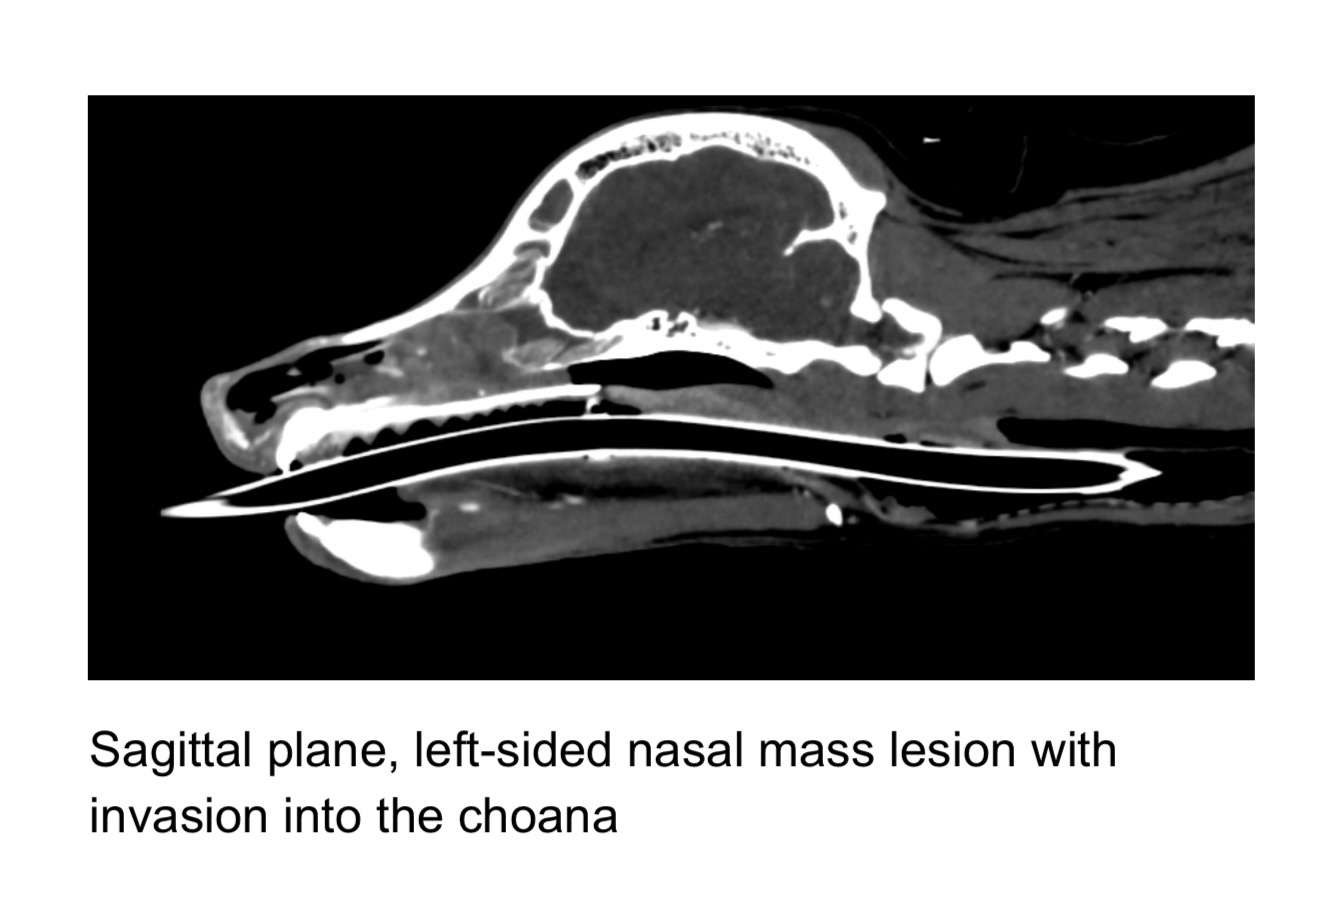

Kuma finished his CT scan and it is confirmed that he had a tumor located in his left nasal cavity. The tumor is over 4cm long slowly moving back towards his brain and down his throat. They are going to blind biopsy the tumor to run some test.

Kumas Dr at VCA sent over the CT scans of Kumas skull. he has a follow up appointment in a month to see how much the tumor has grown. I am currently trying to stop it from getting bigger. Trying all these things that I have been recommended before chemotherapy. He will have another CT scan in one month to see how the tumor is doing.